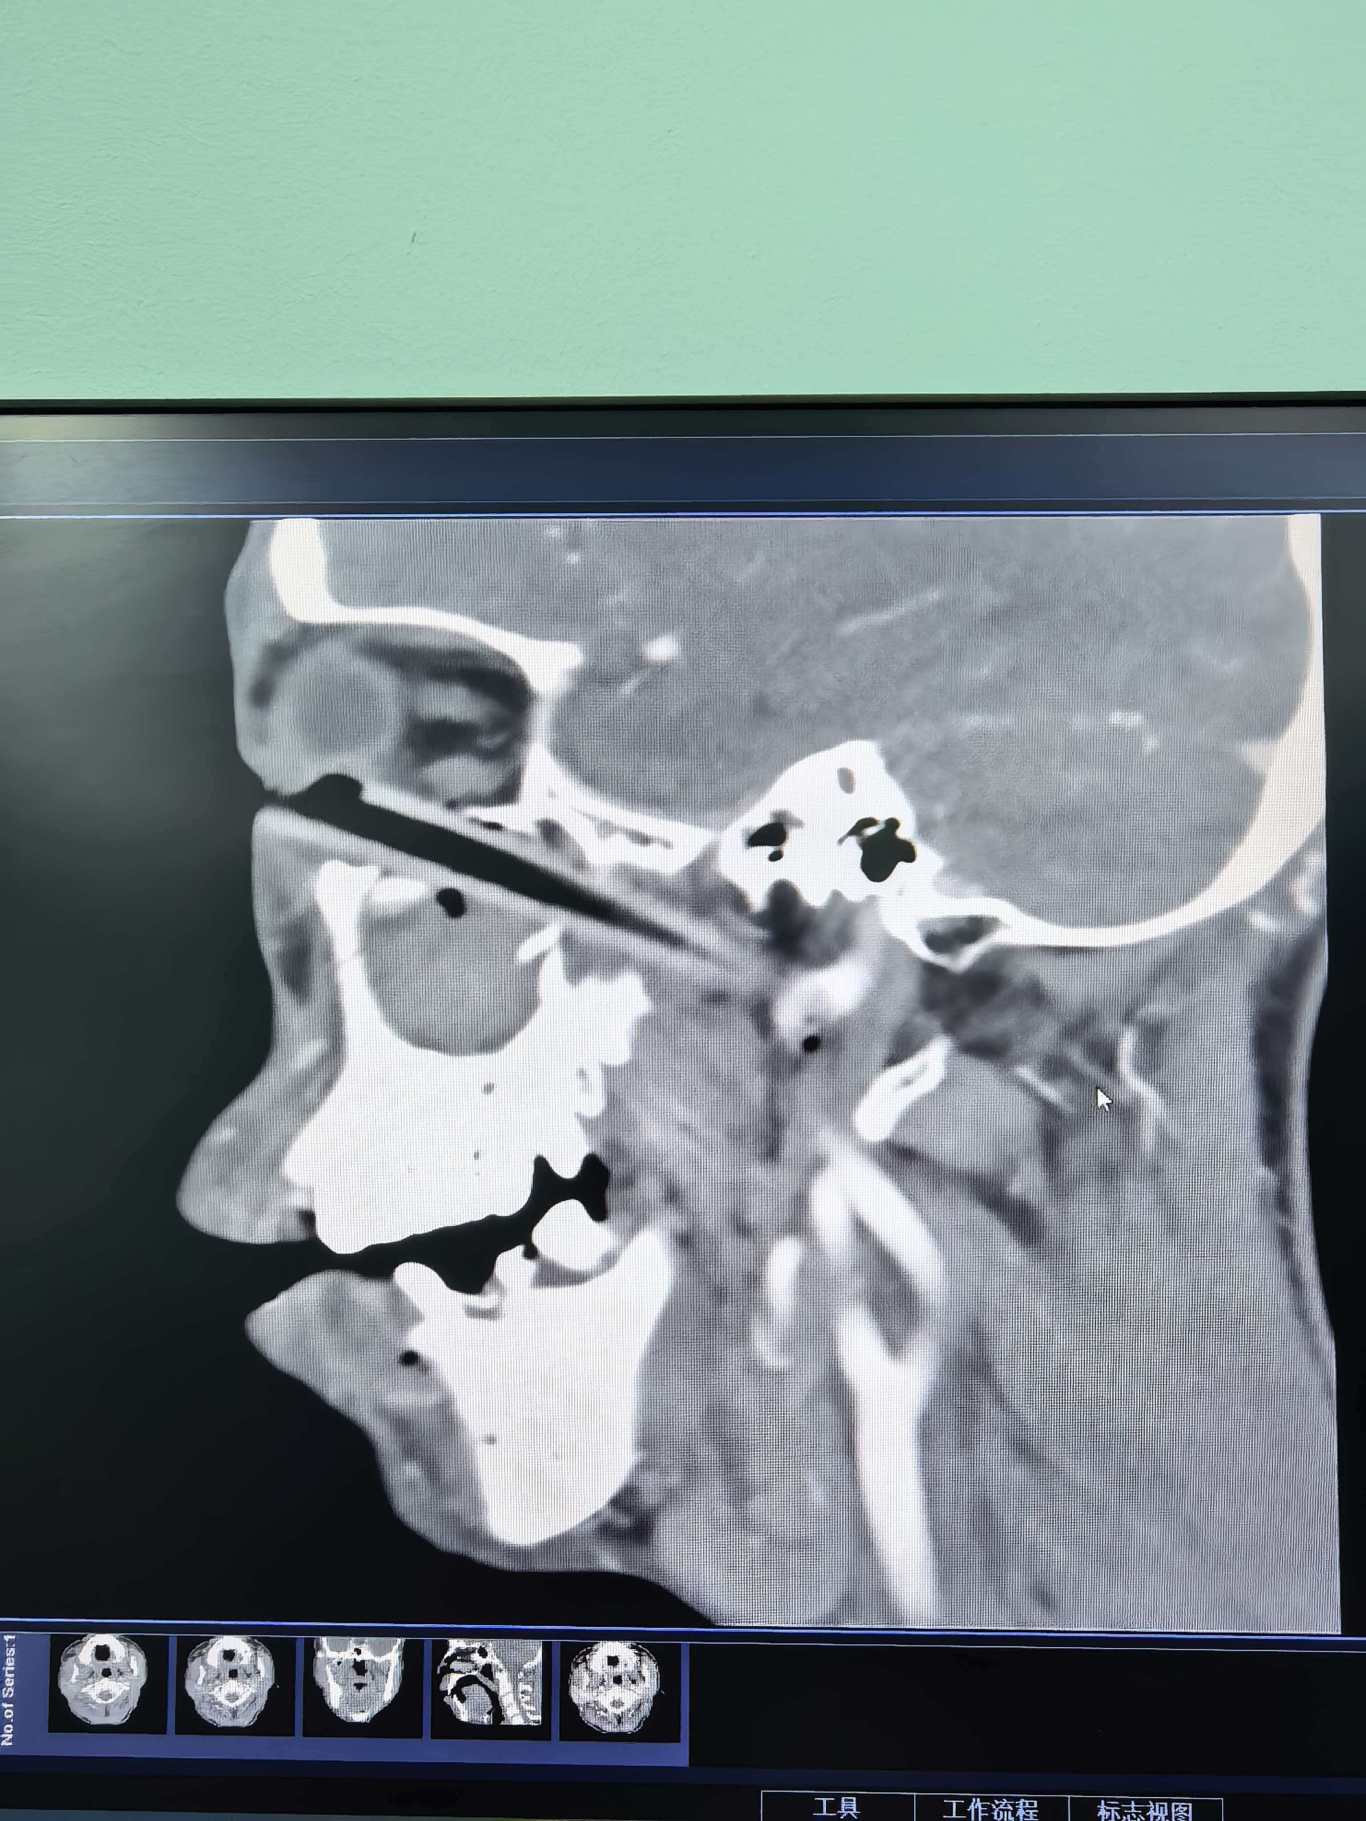

患者龙某近日在干农活时不慎摔倒致右眼被树枝刺入,导致右眼疼痛流血、睁眼困难。医生检查发现右眼眶内有巨大异物残留,其尖端与颈总动脉管壁相贴,十分危险。2月25日上午7:40,眼科联合颅脑外科、介入科、血管外科、口腔颌面外科召开全院MDT会诊讨论,制定手术方案。杨夏带领眼科医师对患者作眼眶开眶术后完整取出长达9cm的木质异物。目前,患者已完成后续治疗痊愈出院,右眼视力恢复到0.6。

2月26日凌晨4时30分,在家休息的杨夏被眼科病房值班医生急促的电话铃声叫醒!颅脑外科收治了一位巨大金属异物右眼眶贯穿到颅腔、副鼻窦、鼻腔、口腔的24岁男性患者,生命垂危,急需眼眶专科及颌面外科、五官科等多学科积极抢救。杨夏为患者成功取出异物,其最长处19cm、最宽处近7cm、最厚处4cm。遗憾的是因右眼球毁损严重只能摘除,术后患者在颅脑外科进行进一步治疗。至3月16日患者生命体征平稳,无感染及脑脊液漏等颅脑并发症,成功保住了左眼球及视力。